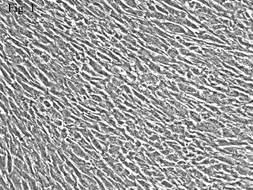

結膜細胞2.眼部的組織病理學改變 多形性紅斑型Stevens-Johnson綜合徵患者急性期眼部可出現非特異性的炎症反應。同時可發生廣泛的小動脈和小靜脈壞死,伴有膠原的纖維素樣變性在疾病的慢性期,角膜、結膜和眼瞼的瘢痕化比較明顯。Stevens-Johnson綜合徵的結膜活檢發現存在杯狀細胞缺失的現象。在Stevens-Johnson綜合徵的急性期是以非特異性炎症細胞浸潤為特徵的,可累及結膜的上皮下層。在上皮下的微血管內發現存在循環免疫複合物。在Stevens-Johnson綜合徵時可有基底部上皮細胞的增殖,而且結膜細胞增殖的程度與疾病的嚴重程度有一定的關係。